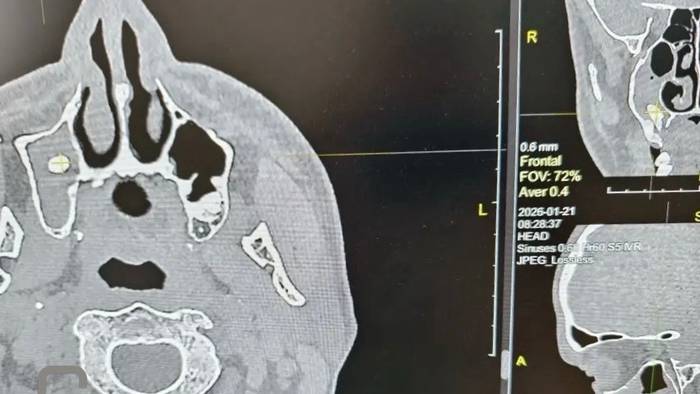

Доктора Орской городской больницы провели уникальную операцию, вернув пациенту способность полноценно дышать. Мужчина обратился в хирургический стационар с жалобами на одышку, однако обследование выявило крайне редкое осложнение: после посещения стоматолога один из зубов «мигрировал» в носовую пазуху.

По словам специалистов медучреждения, на первичной стоматологической процедуре произошла перфорация костной перегородки, разделяющей альвеолярный отросток и гайморову пазуху. Зуб сместился в непривычную анатомическую полость, где застрял, спровоцировав закупорку дыхательных путей.

Операцию по извлечению инородного тела возглавила заведующая ЛОР-отделением Татьяна Смирнова. Использование передового эндоскопического оборудования позволило медикам детально рассмотреть зону вмешательства и действовать максимально аккуратно.

Несмотря на то что зуб глубоко врос в мягкие ткани, что значительно усложняло задачу, хирурги справились со своей работой. После завершения манипуляций дыхание пациента восстановилось в полном объеме. В качестве «трофея» врачи вернули мужчине его зуб.